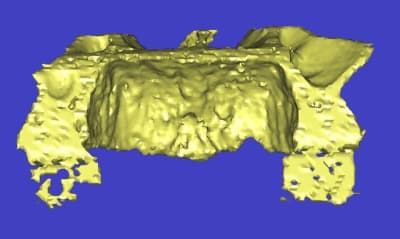

l'étude en partant des blocs standards

La première diapo est un essai pour justifier le concept (os non destiné à une utilisation greffe)

la deuxième est "tapée" dans une tête de femur de mauvais qualité (rejetée)

la troisième et suivante ce sont "les greffons" définitifs.